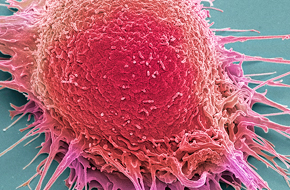

With an industry-leading 3000 PDX models available, we are committed to advancing your preclinical development programs in a timely and cost-effective manner.

Leverage our unrivalled collection of PDX models, derived directly from patient tumors to reflect the heterogeneity and diversity of the human patient population

Make key decisions in a timely and cost-effective manner about the progression of your preclinical development program with cell line-derived xenograft (CDX) models.